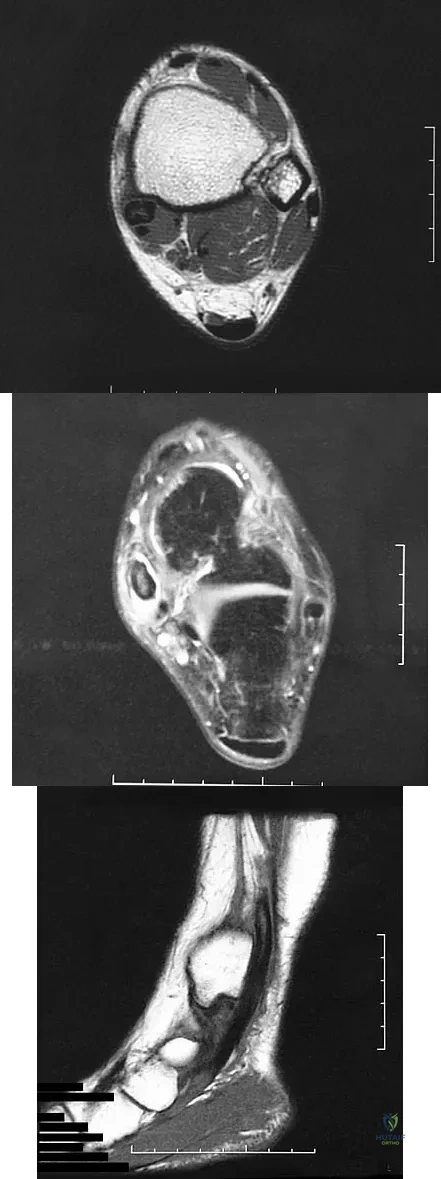

Question 74

A 37-year-old man with a history of congenital flatfoot reports worsening pain on the medial aspect of his ankle for the past year. The pain is worse with weight bearing and is better with rest and the use of an ankle brace. What findings are shown on the MRI scans shown in Figures 18a through 18c?

Explanation